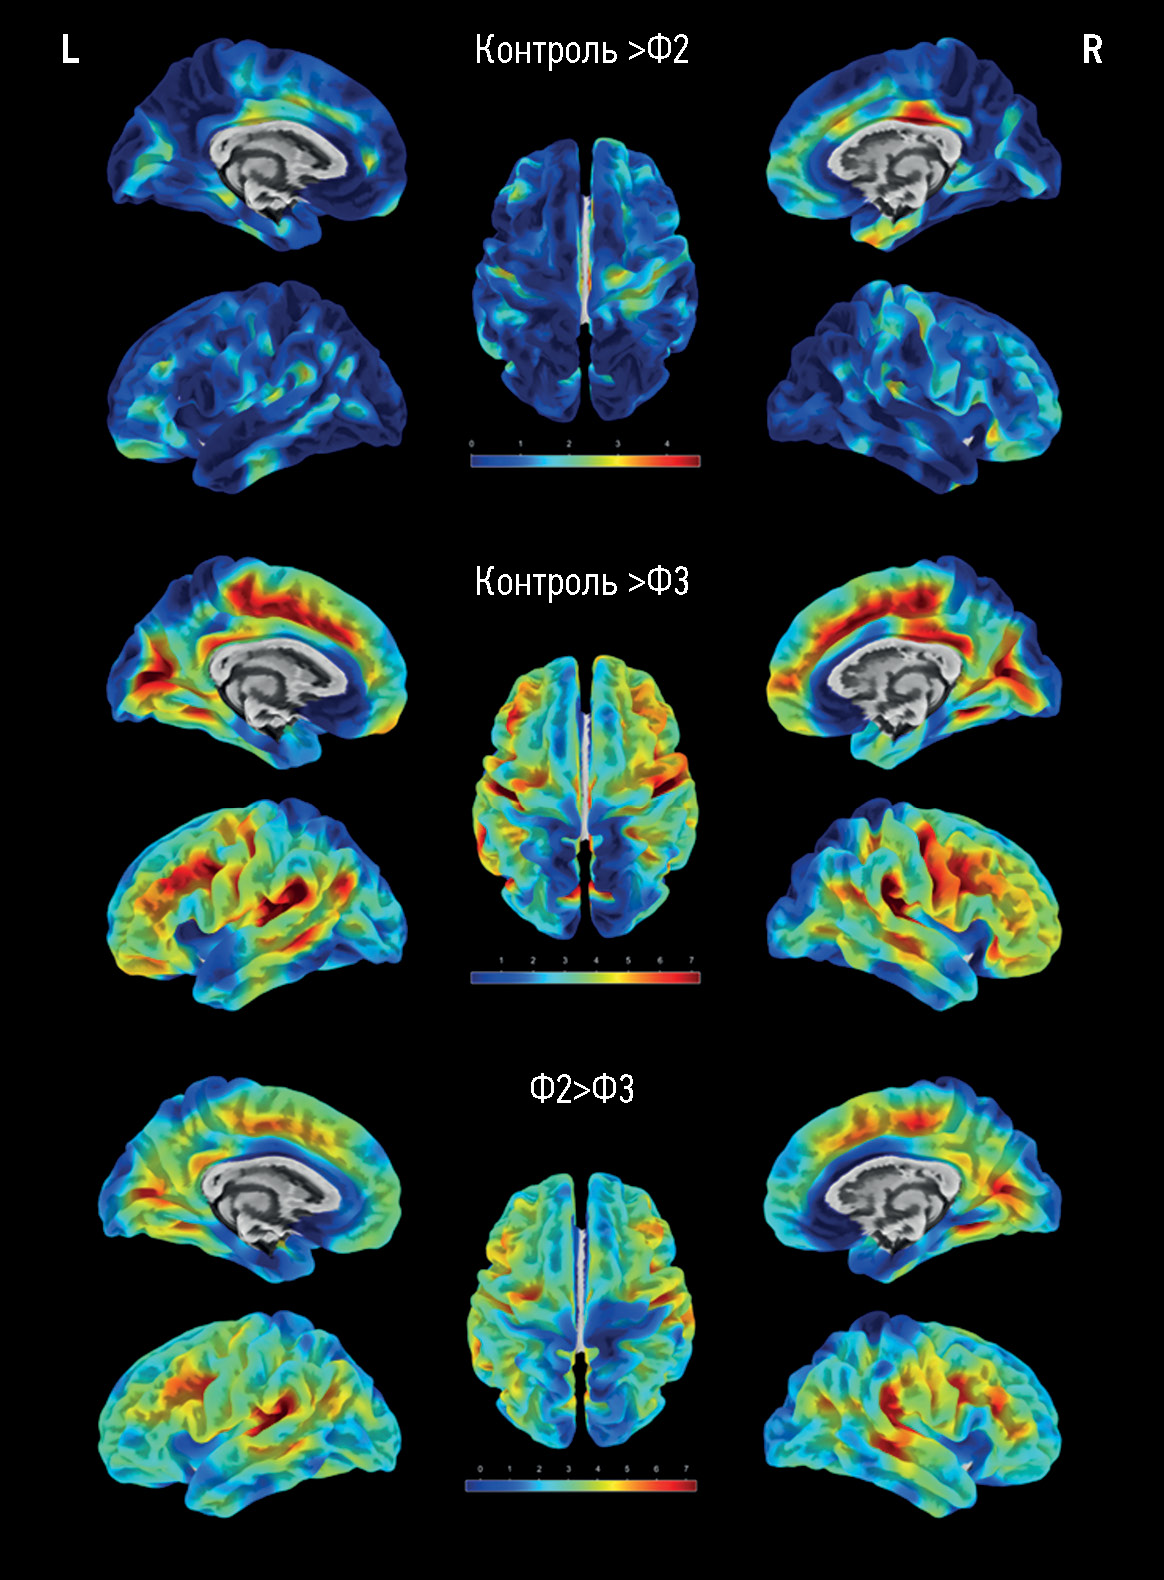

При попарном сравнении изображений групп с разной выраженностью гиперинтенсивности белого вещества значимых (FWE, pcorr <0,05) различий в толщине коры между пациентами группы Фазекас 1 и контролем не было, в группе Фазекас 2 максимально выраженные изменения по сравнению с группой контроля отмечались в центрально-передних и центрально-задних отделах правой поясной извилины (рис. 1). Максимальная разница в толщине коры для групп Фазекас 2 и Фазекас 3 отмечалась в области средних лобных извилин и височно-теменных областях, а также в задних отделах поясных извилин и медиальных отделах лобных долей. Прогрессирование гиперинтенсивности белого вещества до стадии Фазекас 3 по сравнению с группой контроля характеризовалось изменением в более обширных регионах коры (см. рис. 1). Максимальные изменения отмечались в тех же регионах, что и при сравнении групп Фазекас 2 и Фазекас 3 между собой ― в области средних лобных извилин и височно-теменных областях, а также в задних отделах поясных извилин и медиальных отделах лобных долей.

Рис. 1. Визуальное отображение результатов поверхностной морфометрии после статистического анализа изображений групп контроля и Фазекас 2 (первый ряд, Ф2), контроля и Фазекас 3 (средний ряд, Ф3), Фазекас 2 и Фазекас 3 (нижний ряд) в программе CAT12 с выделением красно-жёлтой градации цвета (согласно шкале) регионов со значимо большими различиями толщины коры между группами (FWE, pcorr <0,05). L ― левое полушарие, R ― правое полушарие.